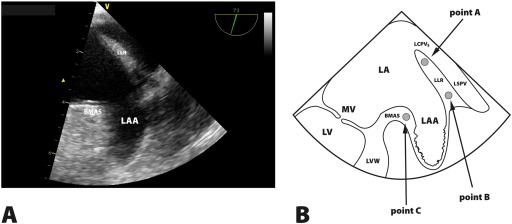

Fig. 2

Fig. 2.

Panel A. LAA structure with its basic segments in TEE (2D). LLR-left lateral ridge, BMAS-baso-medial appendage segment. Panel B. Left atrial appendage longitudinal view in transesophageal echocardiography and regions of interests A, B and C. MVC-mitral valve closure, LA-left atrium, LAA-left atrium appendage, MV-mitral valve, LV-left ventricle, LVW-left ventricle wall, VMV-mitral valve vestibule, LLR-left lateral ridge, LSPV-left superior pulmonary vein, LCPV-left common pulmonary veins.

TDI was performed at a frame rate of over 100 frames per second (fps). During a TEE procedure the patients ECG was recorded. TDI echocardiograms included potential sites for STE analysis within the region of interest and at least three QRS complexes. Measurements were made within LLR near its top (area A) and near its bottom (area B). BMAS was the third point of measurement (area C) (Fig. 2). In order to acquire images at fps > 100 in some cases it was not possible to visualize simultaneously all measurement areas, i.e. A, B and C. For this reason the region of interest (ROI) showing A and B and separately the ROI that included C were selected for analysis. The peak atrial velocity in the middle of LLR was also measured using pulse-wave TDI (PW-TDI) (Fig. 3). This measurement served as the basis for calculating TDI-derived peak velocities. The beam-to-flow deviation in PW-TDI was established. Peak velocities in patients with SR and AF were measured in the same beam positions. In patients with SR and AF peak positive LLR values were measured at 150 ms before the QRS complex. In AF patients measurements were performed when the duration between QRS complexes exceeded 800–900 ms.